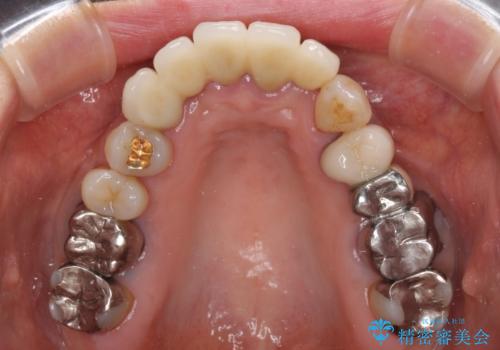

露出していた歯根や金属の縁が見えてしまい、なかなか口を開けて笑うことができなかったのですが、歯肉の位置に縁を合わせることで自然な仕上がりとなりました。

ブリッジの隙間にものが詰まったり、空気が抜けたりすることも無くなり、話しやすさも改善することができました。

露出していた歯根が覆われるため、歯冠が長く見えてしまうことが懸念されましたが特に気になることはなく、患者様には大変満足していただきました。